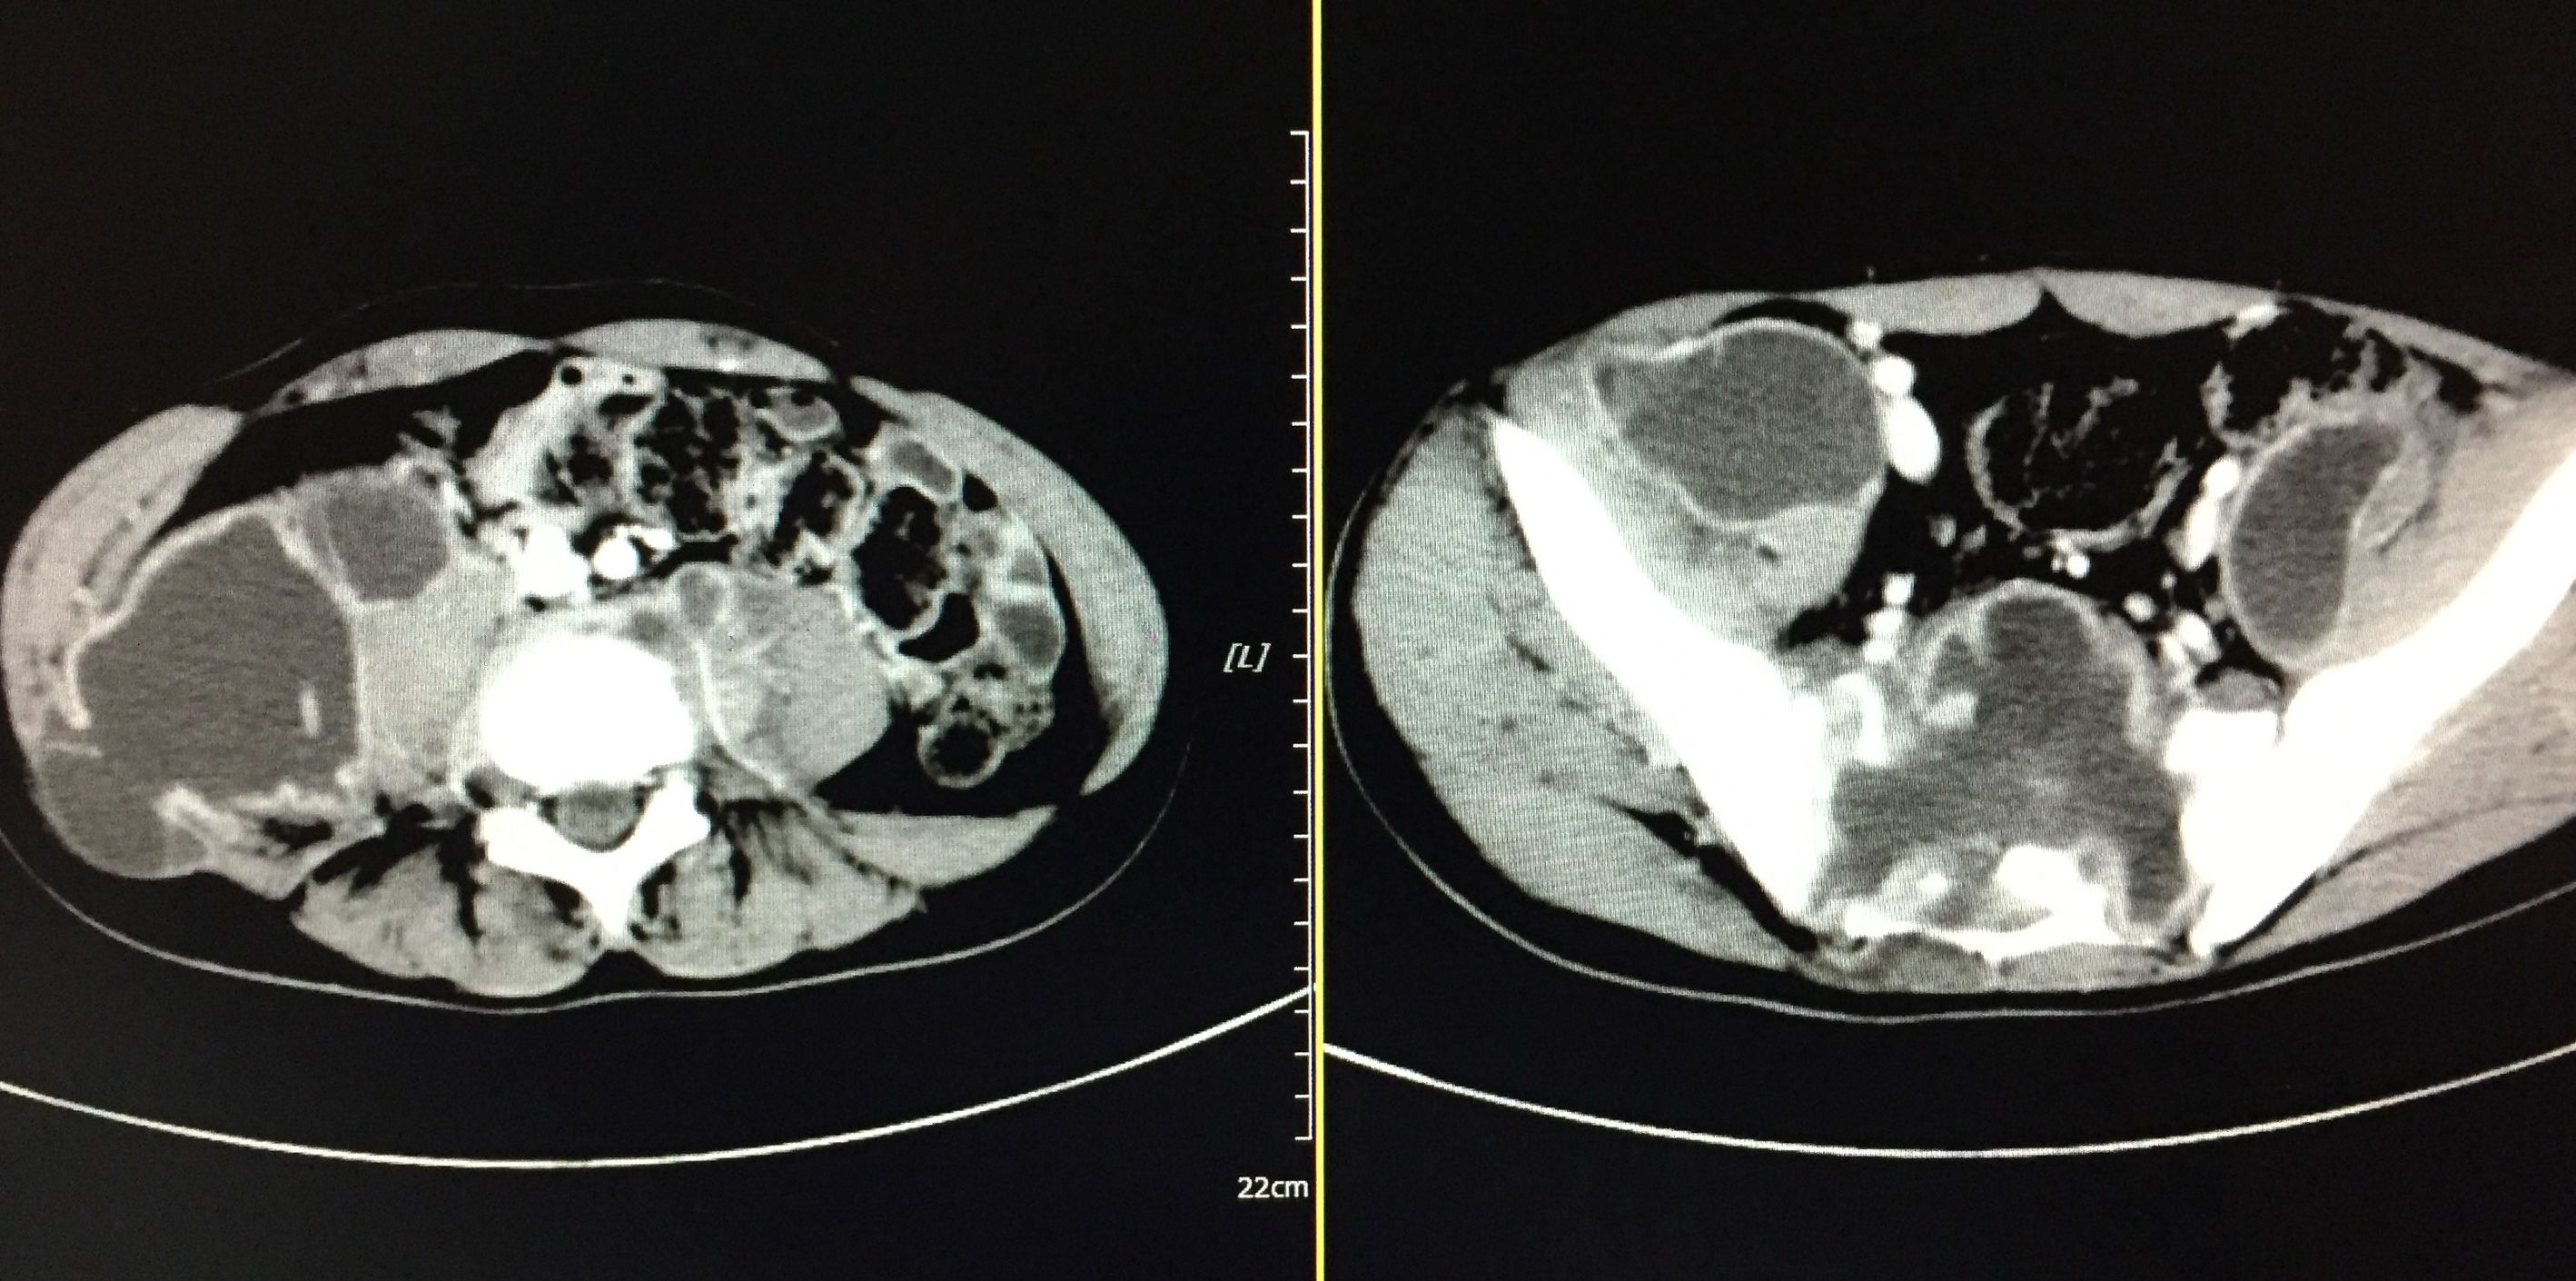

患者 20岁,低热、盗汗半年余,腰骶部疼痛。CT显示盆腔多发结核脓肿,同时骶骨骨质基本破坏,骨盆力学结构受损。

我们对患者在门诊进行充份置管引流(白色条状物5根)

在患者持续引流状态下,并联合抗痨治疗。如下图所示,脓肿完全吸收。患者痊愈。